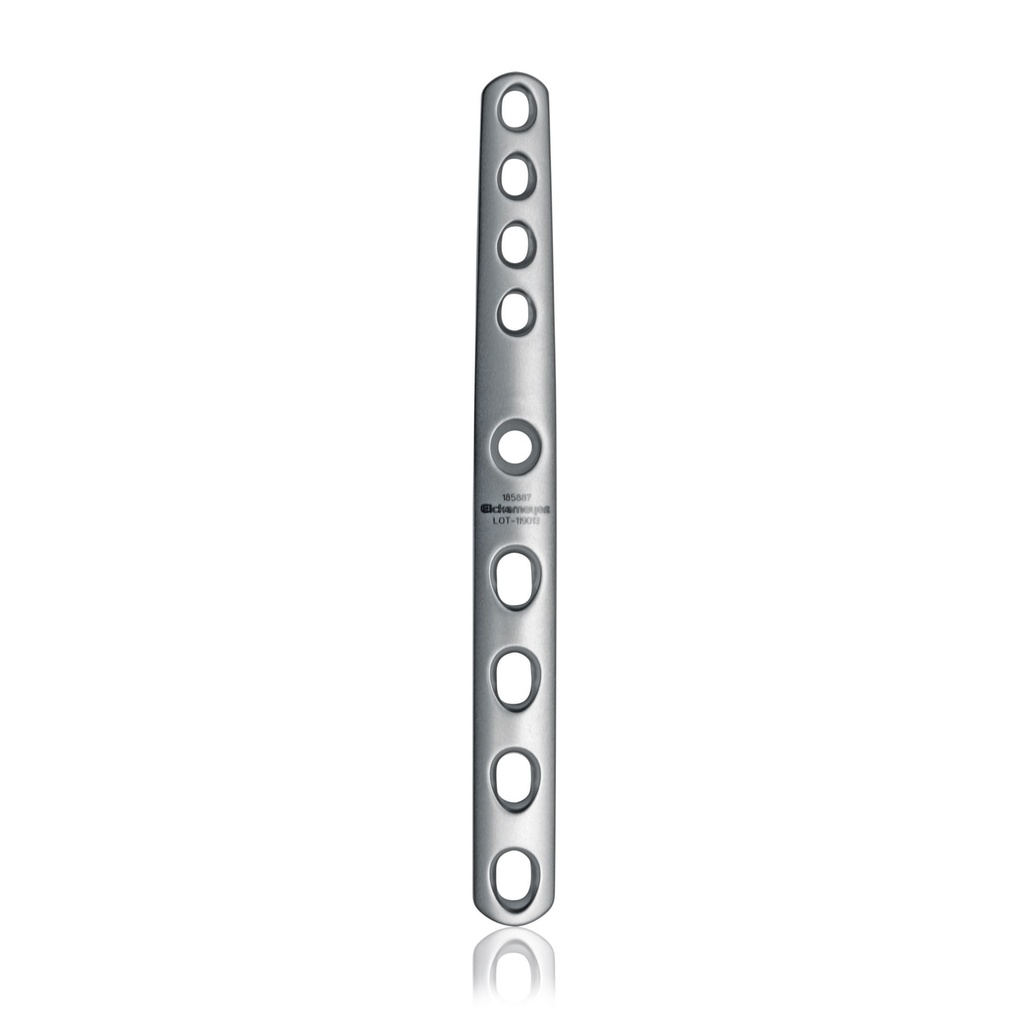

Plate PTA, Pre-Bent, 2.0/2.7mm

Hybrid plates designed with pre-bent 5oangle to encourage fusion of all carpal joints (radiocarpal, middle carpal, and carpometacarpal) at a functional angle.

Plate geometry allows for convenient intraoperative application and minimal soft tissue irritation.

Cortical screws can be placed at variable angles via dynamic compression holes to avoid interference with other screws and engage as many fragments as possible.

- Thickness: 2.0 mm